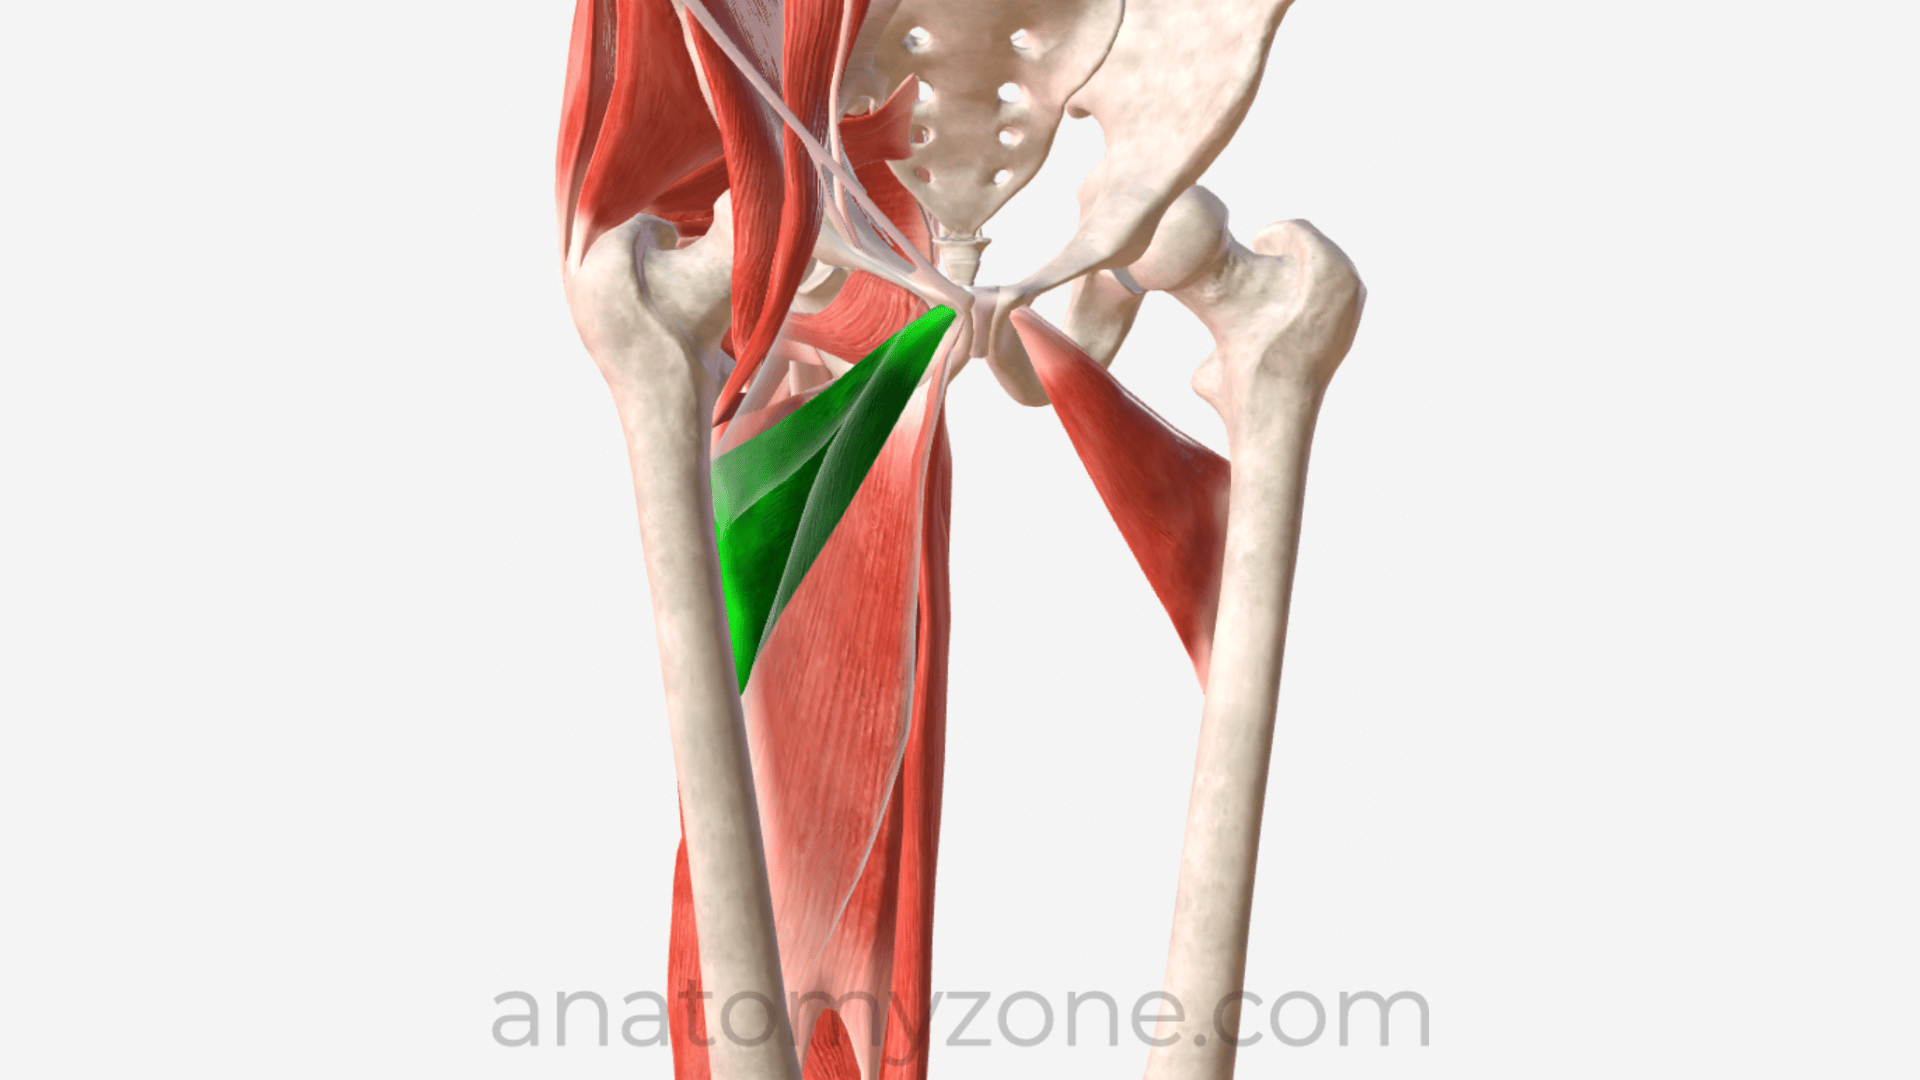

Анатомия и Функции Мышцы Adductor Magnus